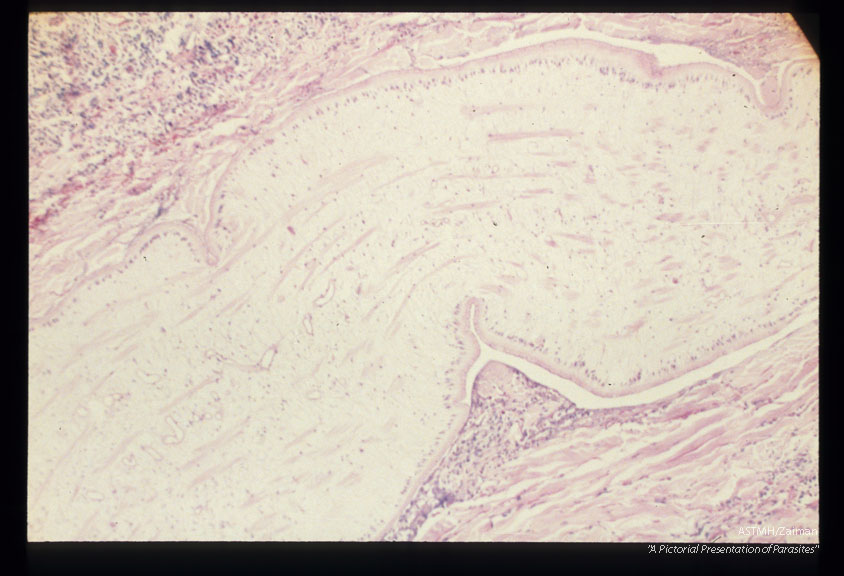

Multiple sections through subcutaneous human tissue containing a sparganum and through the sparganum itself. Note the tremendous inflammatory reaction.

Sparganum

Description: Multiple sections through subcutaneous human tissue containing a sparganum and through the sparganum itself. Note the tremendous inflammatory reaction.